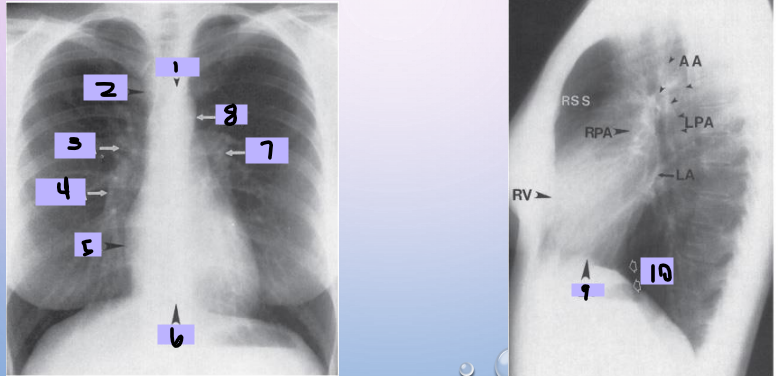

Aortic arch

#1

Superior vena cava

#2

Right pulmonary artery

#3

Right descending pulmonary artery

#4

Right atrium

#5

Right ventricle

#6

Left pulmonary artery

#7

Descending aorta

#8

Left ventricle

#9

Inferior vena cava

#10